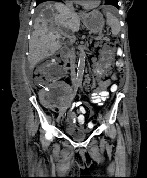

Sarcomatoid Renal Cell Carcinoma in a Renal Allograft

Rajan Kapoor1*, Sandeep Padala1, Carlos Zayas1, Laura Mulloy1, Anusha Vakiti2, Daniel T. Kleven3, Muhammad I. Saeed4, Todd Merchen4